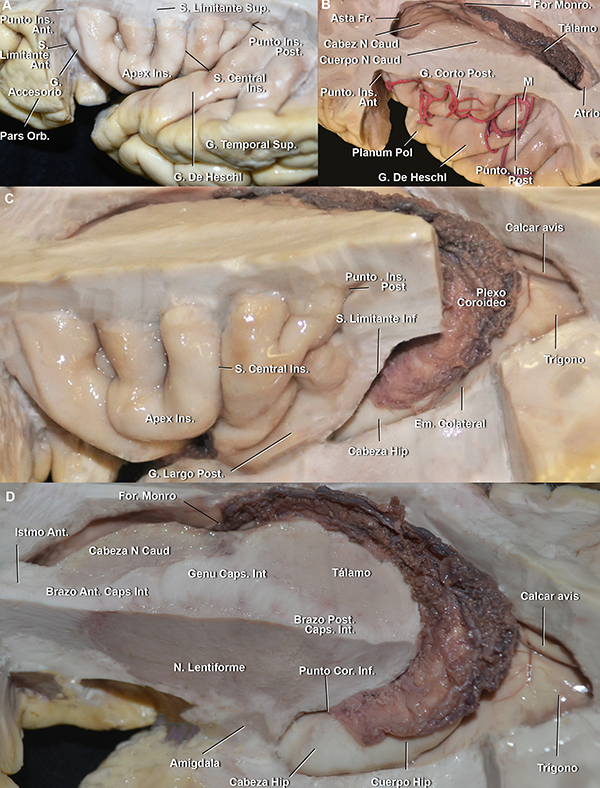

La FS se divide en una sección lateral y una basal. El punto divisor arbitrario entre ellas es el limen insular, definido como un área anatómica arqueada que se extiende desde el punto donde el giro largo insular posterior se fusiona con el plano polar del lóbulo temporal, hasta los giros fronto-orbitarios. El limen insular se relaciona superficialmente con el vértice inferior de la pars triangularis del giro frontal inferior. El mismo oficia como eje para el cambio de dirección de la arteria cerebral media (ACM) (Figura 1).

Figura 1: A. Vista anterior de la superficie basal de una FS derecha. La parte más profunda de la FS en la superficie basal está conformada por el compartimiento operculoinsular anterior. El receso del limen (flecha verde) es el espacio entre el punto más lateral en el que una arteria perforante entra a la SPA y el borde medial del limen insular. B. Vista anteroinferior de un hemisferio cerebral izquierdo. Las estructuras neurales que marcan el límite medial de la parte basal de la cisterna silviana son el tracto olfatorio y la incisura rinal. El uncus se localiza medialmente a la incisura rinal, en relación con la cisterna carotídea. C. Mismo espécimen que en B, vista anterolateral. El disector se ubica en la hendidura insular anterior. En este espécimen la bifurcación de ACM se localiza en el limen insular. Se observa una arteria temporal temprana naciendo de M1. D. Vista anteroinferior de la superficie basal de una FS izquierda. El compartimiento esfenoidal se extiende desde la cisterna carotídea hasta el limen insular. La bifurcación carotídea y la mitad proximal de M1 y A1, se localizan en la cisterna carotídea. El segmento anterior del uncus se enfrenta al segmento proximal de M1. G: giro; Orb: orbitario; Ins: insular; Lat: lateral; Post: posterior; Ant: anterior; Med: medial; Pl: plano; Perf: perforante; Olf: olfatorio; Sust: sustancia; S: surco; Inci: incisura; Seg: segmento; Ped: pedúnculo; Mesen: mesencefálico; R: ramo; Tempr: temprano; Bifur: bifurcación; Art: arteria; Recu: recurrente; comp: compartimiento.

El tronco silviano se extiende hasta la punta inferior de la pars triangularis. En dicho vértice, se originan los tres ramos. Este punto es conocido como punto silviano anterior (Figura 3).

Los ramos de la FS son: 1) el ramo horizontal, 2) el ramo ascendente y 3) el ramo posterior, que cursa entre la parte posterior del opérculo frontoparietal y el temporal, y usualmente finaliza como una bifurcación en el giro supramarginal: el ramo ascendente terminal y el ramo descendente terminal. Este último, suele ser más corto que el anterior y es inconstante. El punto silviano posterior está ubicado en el extremo distal del ramo posterior, en el punto donde los ramos terminales se originan (Figura 3). Se describen dos ramos adicionales que se originan en el ramo posterior: el surco subcentral anterior y posterior (Figura 4A). Estos dos surcos se localizan anterior y posterior al surco central, respectivamente. Por detrás del punto silviano anterior, se encuentra el punto rolándico inferior (Figura 3). El punto rolándico inferior es definido como el punto de encuentro entre el surco central y la FS. Sin embargo, en el 70% de los casos de nuestra serie, el surco rolándico no se intersectó directamente con la FS en la superficie lateral del cerebro. Consecuentemente, el punto rolándico inferior también se refiere al punto de intersección de la proyección del surco central con la FS.

La parte profunda de la FS tiene una organización más compleja. La parte cisternal en la superficie basal del cerebro se extiende desde la estría olfatoria lateral hasta el limen insular (Figura 1A). Está compuesta por 1) el compartimiento opercular anterior, en un nivel intermedio de profundidad, y 2) la hendidura insular anterior y el compartimiento esfenoidal, en el nivel más profundo (Figura 1).

El compartimiento opercular anterior se define como el espacio entre los giros orbitarios posterior y lateral y el plano polar del lóbulo temporal (Figura 5A y 6B). Por otro lado, la hendidura insular anterior se localiza entre la ínsula y los giros orbitarios lateral y posterior (Figura 1C,6B,7A).

El compartimiento esfenoidal presenta una disposición de inferomedial a superolateral. El extremo medial del compartimiento está delimitado por la membrana aracnoidea silviana proximal, que lo separa de la cisterna carotídea y es perforada por el segmento proximal de M1 de la ACM (Figura 8B). La membrana aracnoidea silviana proximal está adherida a la estría olfatoria lateral y a la incisura rinal, o también llamada incisura temporal (Figura 1B y 8B). El segmento anterior del uncus se ubica medial a la membrana silviana proximal. El techo del compartimiento esfenoidal está compuesto por la sustancia perforada anterior (SPA) y los giros fronto-orbitarios. El núcleo caudado y lentiforme, así como también el brazo anterior de la cápsula interna, se localizan por encima del techo de este compartimiento. La pared posterior del compartimiento esfenoidal es el área donde la SPA se fusiona con el lóbulo temporal. El limen insular es su límite lateral (Figura 1A y B). El receso del limen, que es el área comprendida entre la arteria lentículo estriada más lateral y el limen insular, fue hallado en todos los hemisferios estudiados en este trabajo y midió un promedio de 12 mm de largo (Figura 1A). Este receso es un espacio desprovisto de arterias perforantes. El piso del compartimiento esfenoidal es el plano polar. Este compartimiento contiene principalmente: la mitad distal del segmento M1, las arterias perforantes de la SPA, las ramas corticales tempranas de la ACM, los troncos arteriales post bifurcación que pudieran nacer de este segmento si la bifurcación de la ACM fuera proximal al limen insular, la parte distal de la arteria recurrente de Heubner y la vena cerebral media profunda (Figura 1B y D).

Distalmente al limen insular, en la profundidad de los ramos superficiales, presentando una orientación diagonal, se localiza la parte cisternal lateral de la FS. Este segmento es también conocido como compartimiento operculoinsular lateral. Este compartimiento se encuentra compuesto por tres espacios estrechos: 1) el compartimiento opercular lateral, entre el opérculo frontoparietal y temporal, en un nivel intermedio, 2) la hendidura insular lateral y 3) la región retroinsular (Figura 6). Los últimos dos espacios se encuentran en el nivel más profundo de la cisterna silviana. La hendidura insular lateral se localiza entre la ínsula y los opérculos, extendiéndose desde el limen insular hasta el punto en el que los surcos limitantes insulares superior e inferior se conectan, punto conocido como punto insular posterior. Dicha hendidura tiene un bolsillo superior e inferior. La región retroinsular se extiende desde el punto insular posterior hasta el extremo distal de la FS. Esta región se relaciona superficialmente con el giro supramarginal, superiormente, y los giros temporales transversos, inferiormente (Figura 6B).

El compartimiento opercular lateral es más profundo cuanto más distal se diseque la FS.

Figura 4: A. Vista latero inferior de un opérculo frontoparietal derecho. El opérculo temporal, la parte lateral del giro orbitario posterior y la parte posterior del giro orbitario lateral fueron removidas. Cuando el surco central no alcanza a la FS, el giro subcentral es visible en la cara lateral cerebral. En cambio, cuando sí lo hace, como en este caso, este giro se localiza en la profundidad de la fisura. Se observa cómo el ramo horizontal se continúa medialmente con el surco limitante anterior. El ápex insular se localiza superior y posteriormente al polo insular. B. Vista lateral del mismo espécimen. C. Vista de la superficie lateral de la ínsula de otro espécimen. Estrella azul: punto insular anterior. Estrella verde: punto insular posterior. S: surco; G: giro; Ant: anterior; Post: posterior; Op: opercularis; Ram: ramo; Hor: horizontal; Orb: orbitario; Ins: insular

Figura 6: A. vista lateral de un hemisferio cerebral izquierdo. Se removió el opérculo frontoparietal, preservando la pars orbitalis y triangularis. La punta de la pars triangularis se ubica superficialmente al ápex insular e inmediatamente posterior al polo y limen insular. B. Mismo espécimen. La superficie insular anterior enfrenta a los giros frontoorbitarios y el espacio estrecho entre estas estructuras es la hendidura insular anterior (flechas negras). La región retroinsular se extiende desde el extremo posterior de la ínsula al extremo posterior de la FS. S: surco; G: giro; Ins: insular; Sup: superior; Ram: ramo; Term: terminal; Asc: ascendente; Desc: descendente; Op: opercularis; Orb: orbitalis; Tri: triangularis; Hor: horizontal

Figura 7:A. vista lateral del lóbulo insular izquierdo del mismo espécimen que en la figura 1D y 9D. La superficie lateral de la ínsula está totalmente cubierta por M2 y sus ramas. El limen insular (círculo sombreado azul) limita la parte basal de la lateral de la FS y el segmento M1 de M2. Las arterias corticales tempranas no tienen un segmento insular dado que nacen del segmento M1 y pasan directamente al M3. B. Vista superior del mismo espécimen. El opérculo frontoparietal fue removido. C. Vista inferior de la ínsula del mismo espécimen. Los giros cortos tienen una dirección hacia el ápex insular. Debajo del ápex, la proyección inferior de los giros cortos se dirige hacia el polo insular. Los giros posteriores largos empiezan en el plano polar como un giro único que luego se divide en dos. S: surco; G: giro; Ant: anterior; post: posterior; Ins: insular; Acc: accesorio; Tran: transverso; Inf: inferior; Sup: superior; Orb: orbital; Hend: hendidura; Tempr: temprana.

Figura 9: A. Vista latero superior, quirúrgica, de una FS izquierda (mismo espécimen que en Figura 1B y C). Cabeza de flecha azul: limen insular. El limen insular se encuentra medial y anterior a la punta de la pars triangularis. A su vez, el polo insular se encuentra superolateral al limen insular y el ápex insular, superolateral al polo. Cuanto más posterior en la cisterna silviana, más profundo es el compartimiento opercular. Posterior al giro de Heschl, el opérculo temporal tiene una dirección recta en el plano axial, haciendo más dificultosa la apertura de la FS. B. Vista aumentada de A. C. Vista anterolateral de un hemisferio derecho. El opérculo frontoparietal fue removido. La bifurcación de la ACM se localiza proximal al limen insular (cabezas de flecha azul). D. Vista superolateral del mismo espécimen que en Figura 1D y 7. Las ramas corticales tempranas de la ACM pasan por el limen insular, así como los troncos postbifurcación. Ins: insular; G: giro; Bifur: bifurcación; S: surco; Orb: orbitalis; Fronto Orb: frontoorbitario; R: ramo; Tempr: temprano; Op: opercularis; Tri: triangularis; Pl: plano; Lim: limitante; inf: inferior.